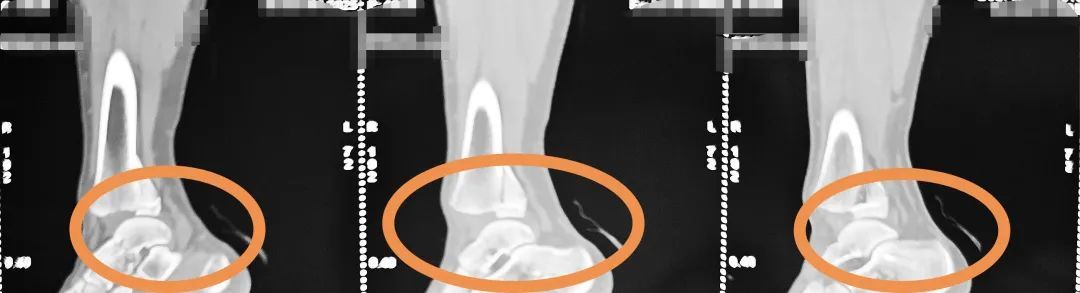

术前侧位图

术前正位图

明确诊断为

右侧胫腓骨远端粉碎性骨折

累及骨骺、关节面